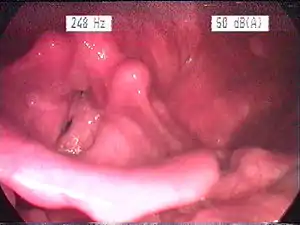

Endoscopic image of an inflamed larynx caused by acid reflux | |

The larynx itself will often show erythema (reddening) and edema (swelling). This can be seen with laryngoscopy or stroboscopy (method depends on the type of laryngitis).[7]: 108 Stroboscopy may be relatively normal or may reveal asymmetry, aperiodicity, and reduced mucosal wave patterns.[22]